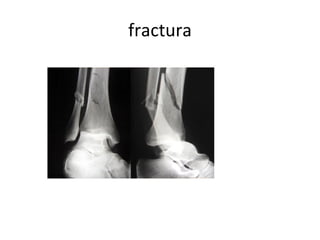

El documento habla sobre la higiene deportiva y los primeros auxilios. Recomienda prevenir lesiones calentando, hidratándose y usando equipo de seguridad. También menciona ducharse con chanclas y ropa seca después del deporte, mantener una buena postura y cómo tratar lesiones comunes como tirones musculares, esguinces y deshidratación. Además, da consejos sobre hemorragias nasales, crisis asmáticas y fracturas.